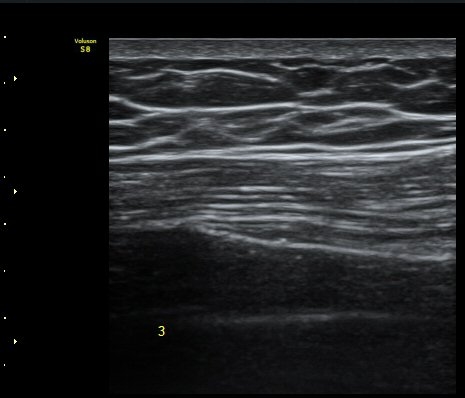

ÇÑ´Þ ÈÄ ÃßÀû°Ë»ç

Á¾´Ü¸é°Ë»ç¿¡¼­ °¡°ñ Çü¼ºÀÌ °üÂûµÊ(formation of callus)   »çÁø 3

°¥ºñ»À Ⱦ´Ü¸é°Ë»ç¿¡¼­ °¡°ñ Çü¼ºÀÌ °üÂûµÊ(formation of callus)  »çÁø 4